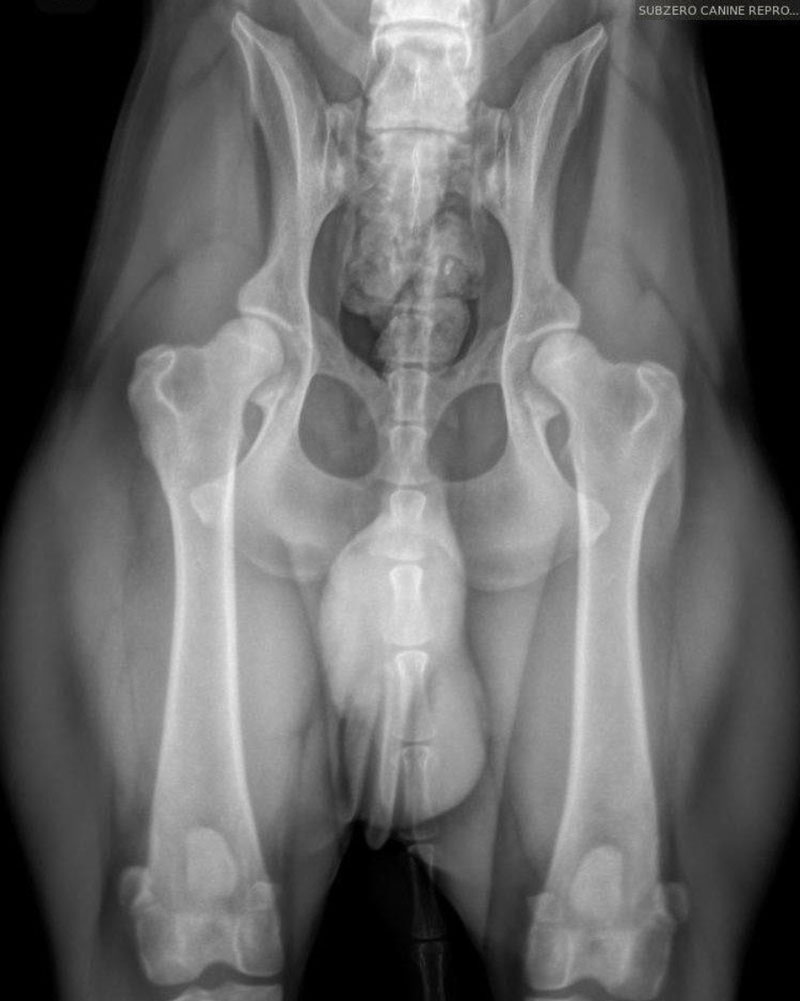

We are proud to offer state of the art Idexx radiology technology and equipment, which allows the clearest of images to be provided to our clientele. This is especially helpful when needing to determine final puppy count prior to whelp. The best time to perform a pregnancy radiograph is 55 days or later from breeding. An appointment is required for this service.

We are also proud to offer OFA (Orthopedic Foundation for Animals) image submissions. This is a requirement amongst many AKC breed clubs and may include several different image types such as:

We frequently receive inquiries regarding our success with proper positioning for OFA images, specifically for hips. Translating this success can be challenging, so we have included images of various breeds that we have taken. We take great pride in our success with these images and many others like them. As extreme perfectionists, we appreciate owners who understand that we strive for the best technique and outcome while minimizing stress and ensuring the comfort of your dog(s), particularly since all images taken here are done WITHOUT sedation.